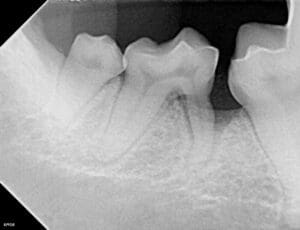

When a dog aggressively chews on a stick, small pieces of wood can break off and get stuck between the teeth. Usually this happens near the back of the mouth, as the premolars and molars are the main teeth used for chewing. Unlike a person, a dog isn’t going to reach for a toothpick, and it is easy for this to go unnoticed. Over time, the presence of this material (called a foreign body), causes inflammation and infection which can lead to periodontal disease and severe bone loss. In severe cases, this can become so advanced that nothing can be done but extract the affected teeth.

X-ray of the same dog showing significant bone loss around the mesial (front) root of the right mandibular second molar.